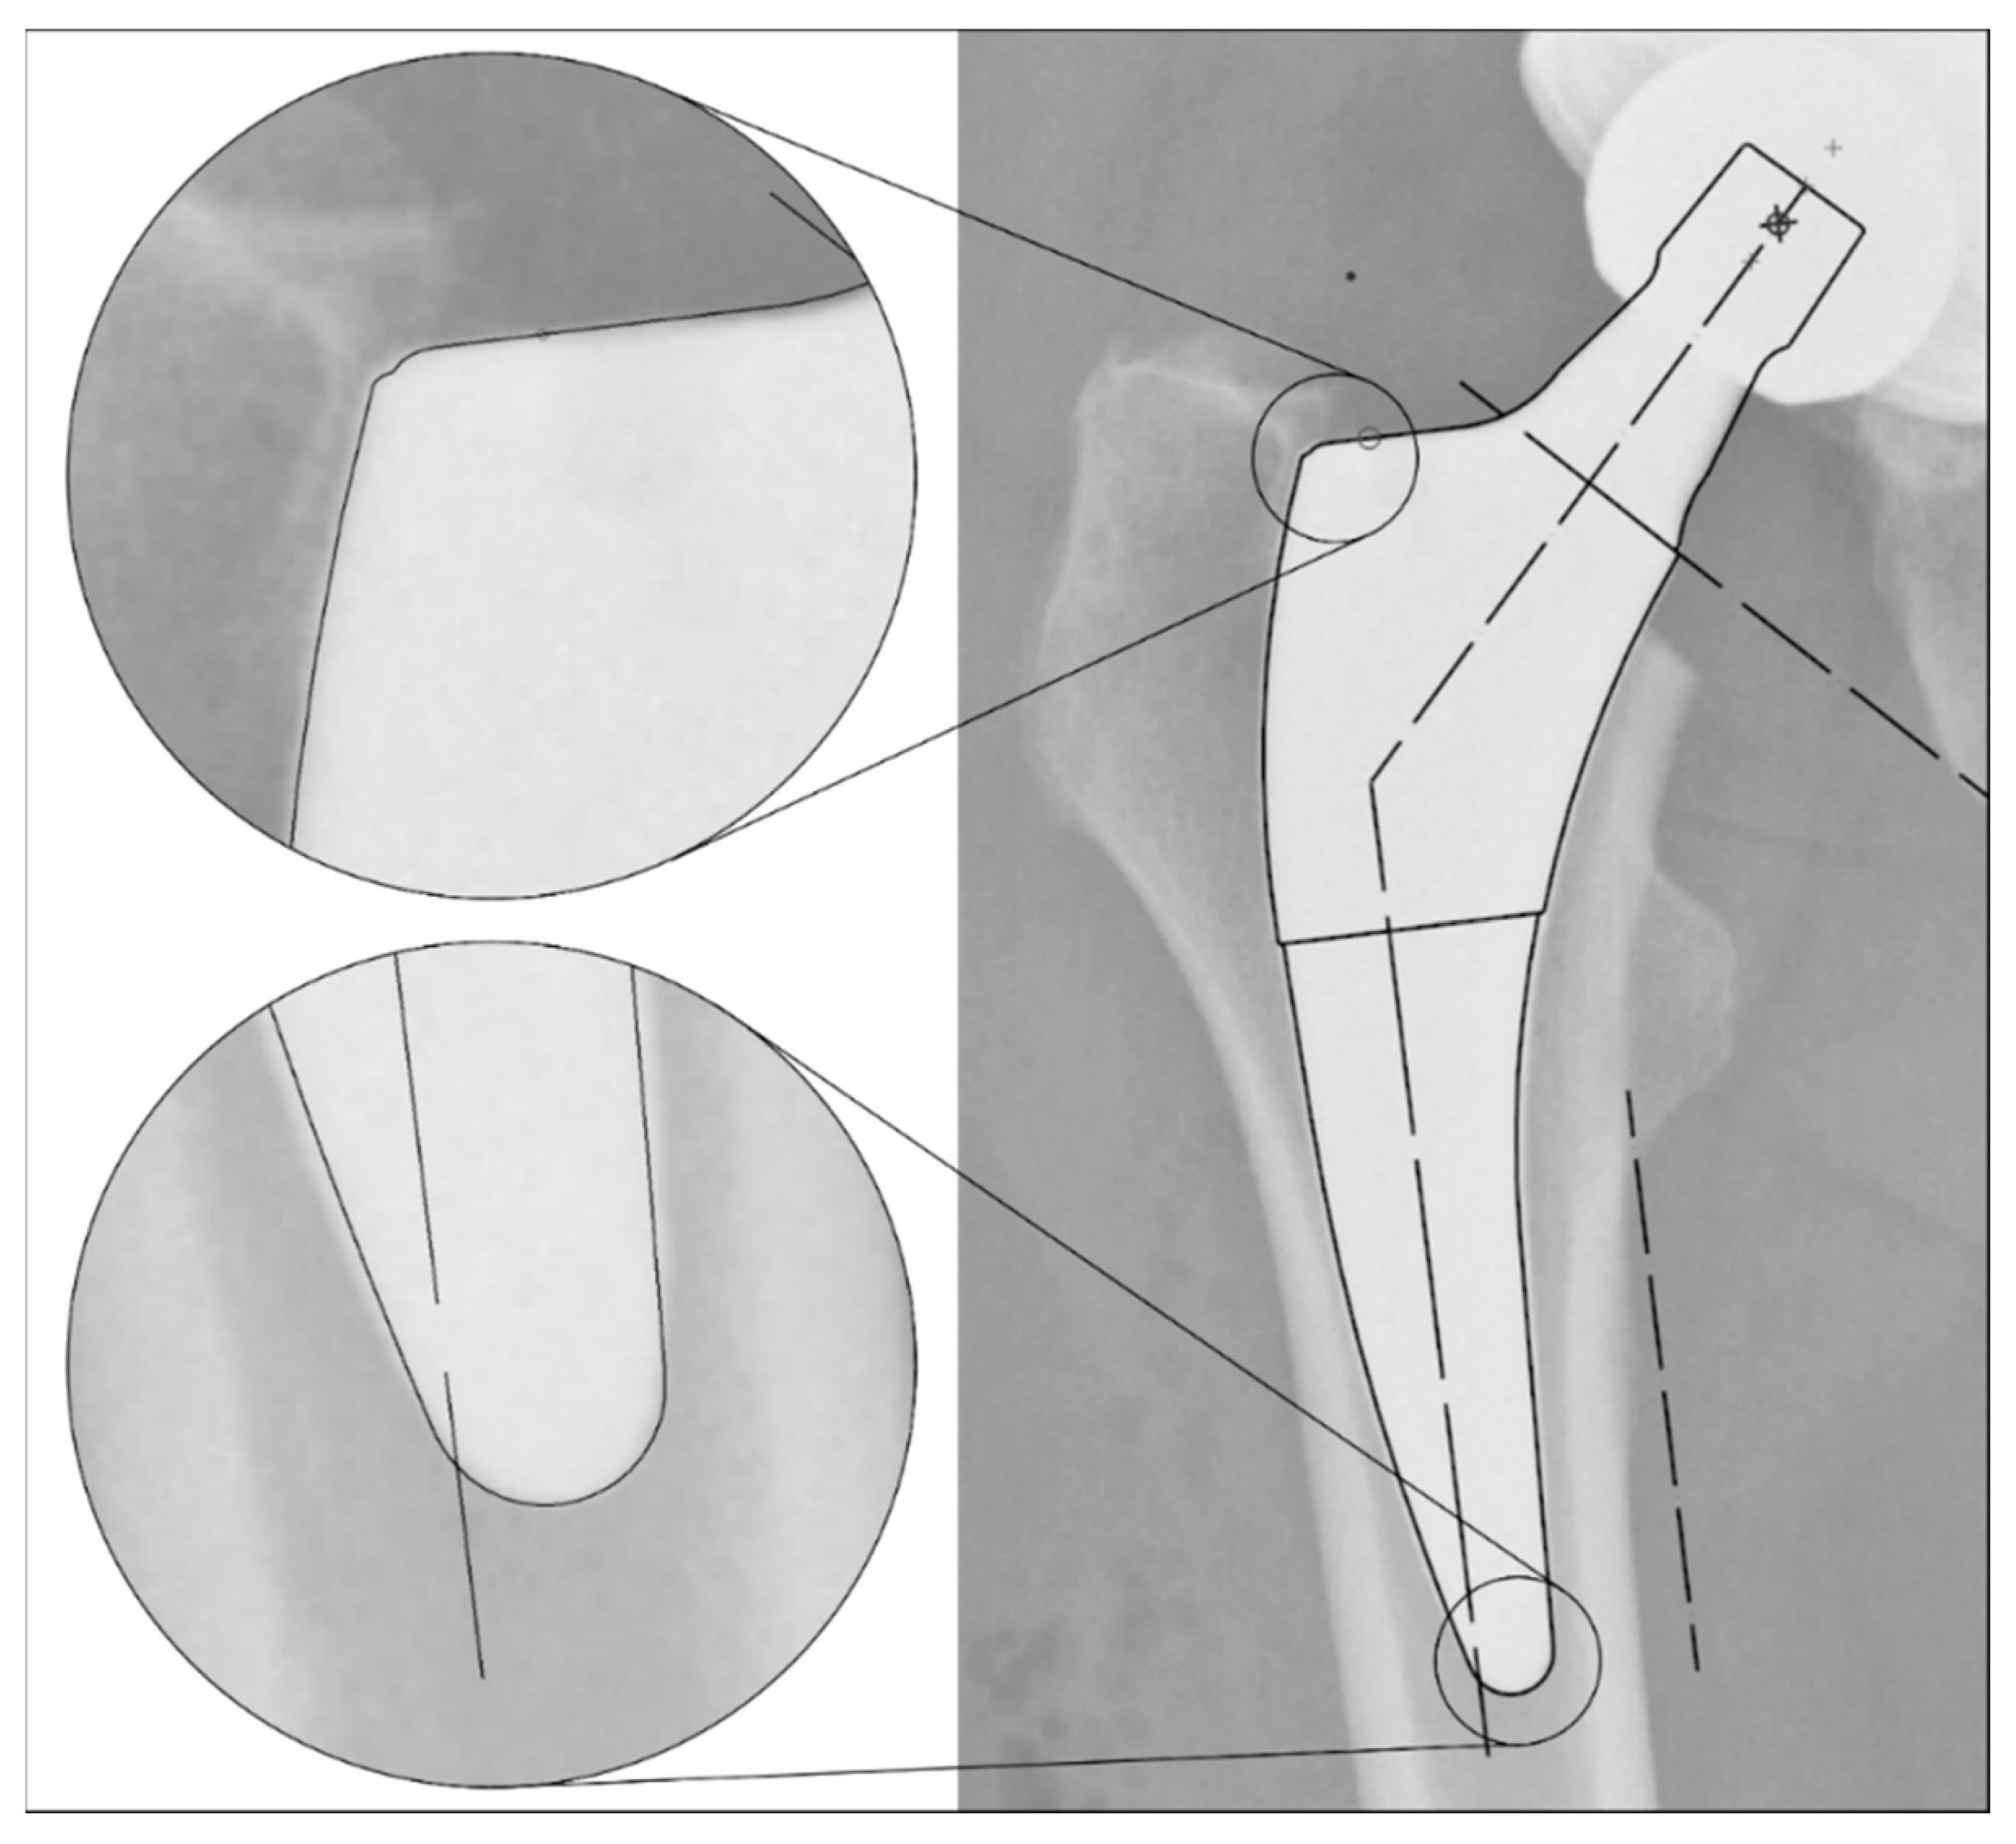

The radiographs were analysed with TraumaCad® software (Brainlab AG, Munich, Germany). We used only standardised deep-centered anteroposterior X-rays of the pelvis, with the central beam perpendicular to the midline and centered over the symphysis, and the legs positioned in 15° of internal rotation with the patient in the supine position. The images were calibrated by measuring the length of the depicted stem from its shoulder to its tip and equating it with the corresponding planning template. In this way, we could avoid any possible errors in our established calibration method with a reference sphere, which can be placed too far away from the central beam or too far away from the film. The measurements of the stem position were subsequently taken on the same axis to neutralise distortions caused by varying flexion and rotation positions of the leg during radiography (Figure 2). The varus/valgus alignment of the stems was determined by measuring the angle between the longitudinal axis of the stem and the longitudinal axis of the femoral canal (Figure 3). Subsidence was determined by measuring the distance from the shoulder of the stem to a clearly definable point at the greater trochanter in the previously determined longitudinal axis of the stem (Figure 4). Due to possible osseous changes over time, such as enthesiopathies or ossifications at the tip of the greater trochanter, defining this point was crucial to measure the correct distance.

Figure 2. Method for calibrating the X-ray images: Equating the maximum length of the stem (from the shoulder to the tip) in the X-ray image to the template size known from the surgical report. This enables a comparable distance measurement even with different X-ray projections due to different rotation and/or varus/valgus position of the leg.